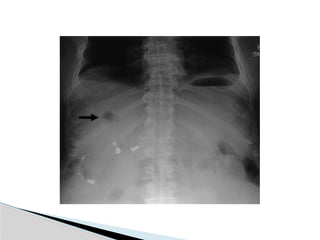

Chest X-ray

 Basilar atelectasis

 Right hemidiaphragm elevation

 Right pleural effusion are present in

approximately 50% of cases

 Before advancements in radiologic technique,

these served as diagnostic clues.